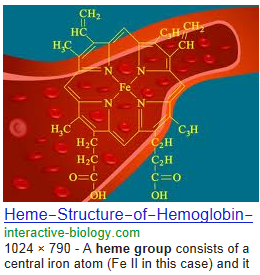

Heme | definition of heme by Medical dictionary

Heme binds and carries oxygen in the red blood cells, releasing it to tissues. Also spelled haeme. See also hemoglobin, porphobilinogen, protoporphyrin.

Heme | definition of heme

Heme | definition of heme OUTPUT formats

Heme | definition of Theme …. SCheme

….. blood IRON Heme Fe(2) group software / the living languages

Fe = Ferrous oxide IRON software ….